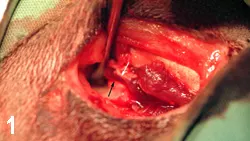

animal was anesthetized for further evaluation of the oral cavity. An open caudal fracture of the left mandibular ramus was visible between the 4th premolar and the 1st molar (Figure B; white arrows). The mandibular artery had been lacerated, and an organized fibrin clot was present (black arrow). An intraoral occlusal view radiograph was taken of the symphysis, and an extraoral lateral radiograph was taken of the TMJ and horizontal ramus of both right and left sides. A 1-cm separation of the symphysis was visible on the films, but no rostral mandibular fractures were present (Figure C). The left lateral film showed a caudal ramus fracture between the 4th premolar and the 1st molar (Figure D). There was no evidence of roots in the fracture site. This film also showed a left craniodorsal TMJ luxation (black arrows) and a left caudal ramus fracture between the 4th premolar and the 1st molar (white arrows).

The ProcedureThe TMJ was approached through a lateral skin incision along the caudoventral margin of the zygomatic arch. A periosteal elevator was used to lift the condylar head (Figure 1; black arrow) into the temporal fossa (white arrow). The masseter muscle was reflected ventrally, and the damaged TMJ joint capsule was visualized by having an assistant open and close the jaw. The dorsocranially deviated condyle was reduced into the temporal fossa. A small hole was drilled through the lateral condyle and fossa by using a no. 1 round bur in a high-speed dental handpiece. A 4-0 nonresorbable nylon was threaded through the predrilled holes, and a simple interrupted knot was tied (Figure 2). Because there was no overlying musculature around the severely damaged joint capsule, imbrication was impossible. A postreduction extraoral radiograph indicated successful reduction (Figure 3).